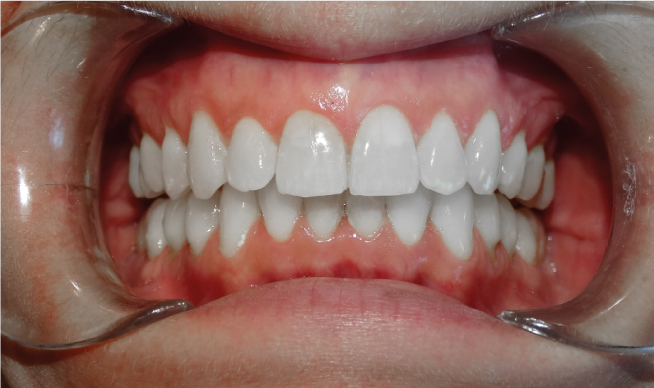

la présence d’une supraclusion, cela signifie que le recouvrement des incisives inférieurs par les incisives supérieures est trop important. Autrement dites, les dents du dessus « cachent » celles du bas, c’est pourquoi on parle aussi de recouvrement dentaire. La supraclusion se manifeste par un recouvrement trop important des incisives inférieurs par les incisives supérieures. Les dents du dessus « cachent »les dents du bas. Ce trouble est fréquent et est aisément traitable grâces aux nouvelles techniques d’orthodontie. Grâce aux nouvelles techniques d’orthodontie, le traitement est facilité́. Il n’est plus nécessaire de porter des « casques » externes et il est très rare d’extraire des dents. Le port de rackets (les « bagues ») permet de résoudre le problème chez l’enfant et l’adulte.